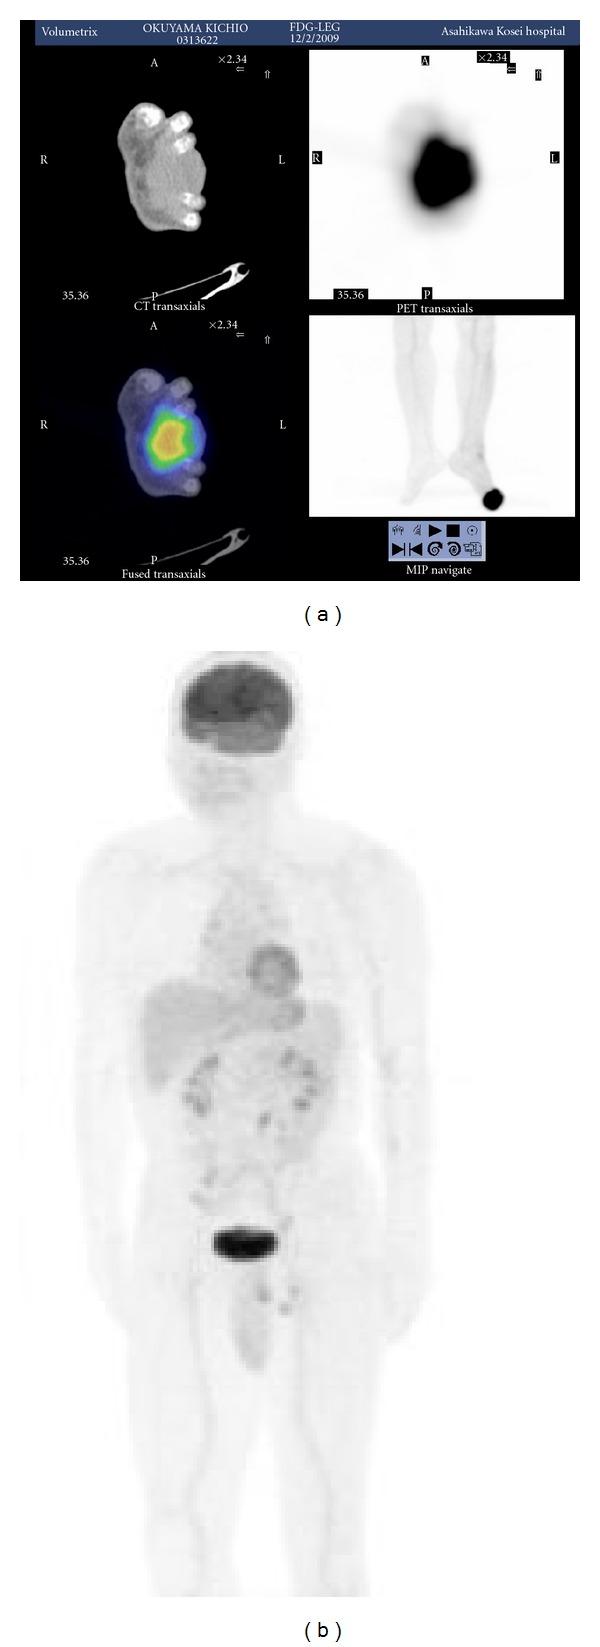

Malignant peripheral nerve sheath tumor (MPNST) is a rare high-grade soft tissue sarcoma. The epithelioid variant accounts for 5% or less of MPNSTs; the clinical behavior of this variant is unclear. Reports of approximately 40 cases are available in the English literature; however, most reports addressed clinicopathological features rather than therapeutic procedures or clinical courses. We describe a case of a 62-year-old male with an epithelioid MPNST of the left foot. Multiple lung metastases developed after radical surgery on the primary lesion. The response to adjuvant chemotherapy including doxorubicin and ifosfamide was favorable, and thoracoscopic resection was subsequently performed on the remaining three metastases. No evidence of recurrence or metastasis was observed at the 12-month followup after the first operation. Further followup and chemotherapy may be required.

摘要

恶性外周神经鞘膜瘤(MPNST)是一种罕见的高级别软组织肉瘤。上皮样变体占MPNST的5%或更少;该变体的临床行为尚不清楚。英文文献中有大约40例相关报道;然而,大多数报道关注的是临床病理特征,而非治疗方法或临床病程。我们描述了一例62岁男性,患有左足上皮样MPNST。原发灶根治性手术后出现了多发肺转移。对包括阿霉素和异环磷酰胺在内的辅助化疗反应良好,随后对其余三处转移灶进行了胸腔镜切除术。首次手术后12个月的随访未发现复发或转移迹象。可能需要进一步随访和化疗。